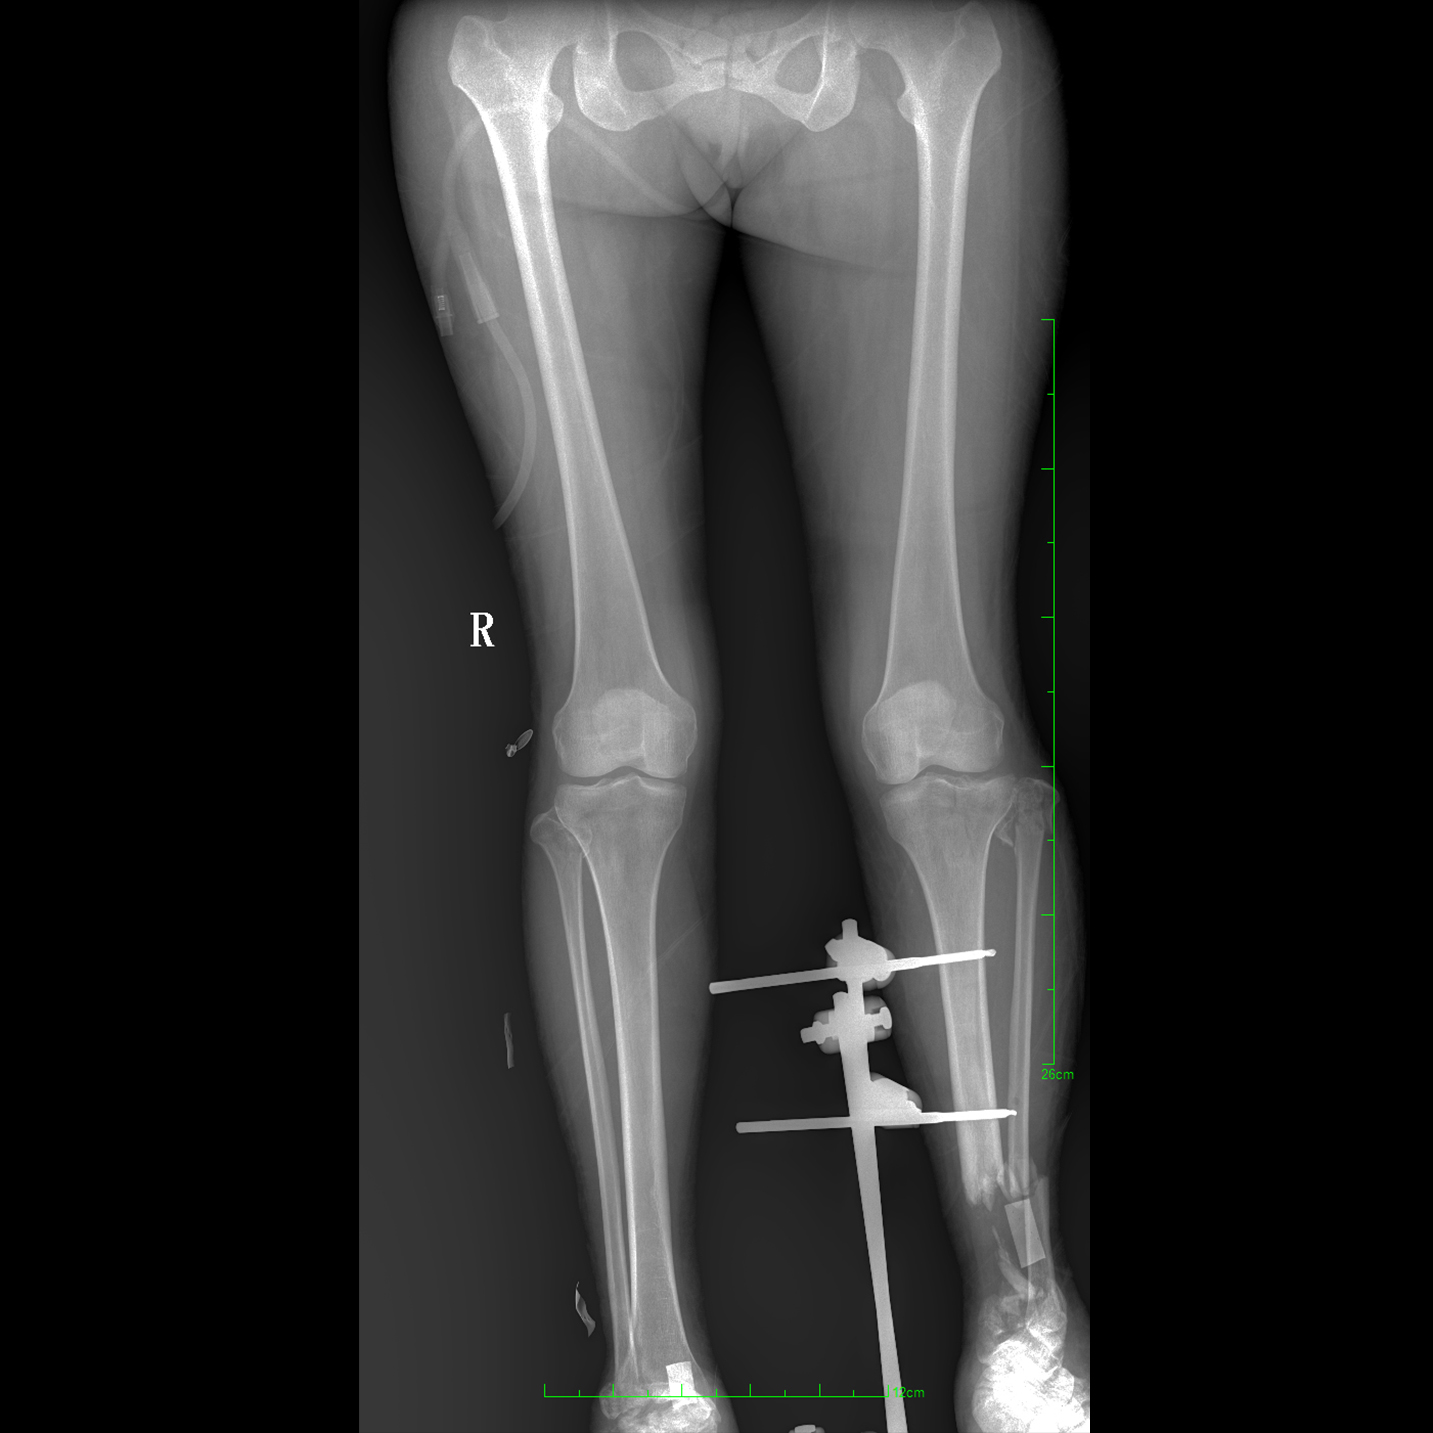

17"*34"有效視野,一次成像不拼接。相較于多張攝影再軟件拼接的DR設(shè)備,PLX8600解決了拼接圖像存在密度不均勻,拼接處圖像配準(zhǔn)和放大效應(yīng)等問題,給臨床帶來了大視野影像解決方案,可一次性覆蓋全脊柱或雙下肢影像。